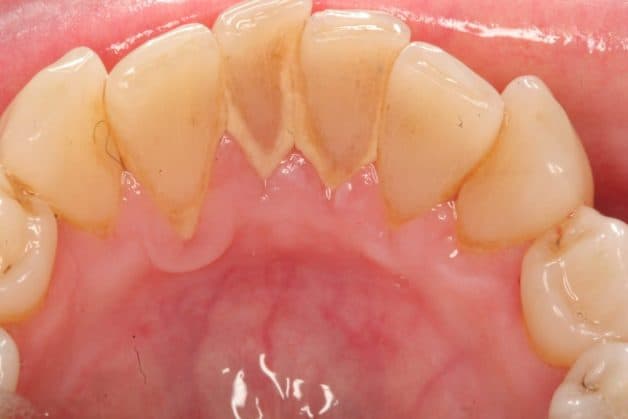

Cao răng đóng thành mảng ở cổ răng